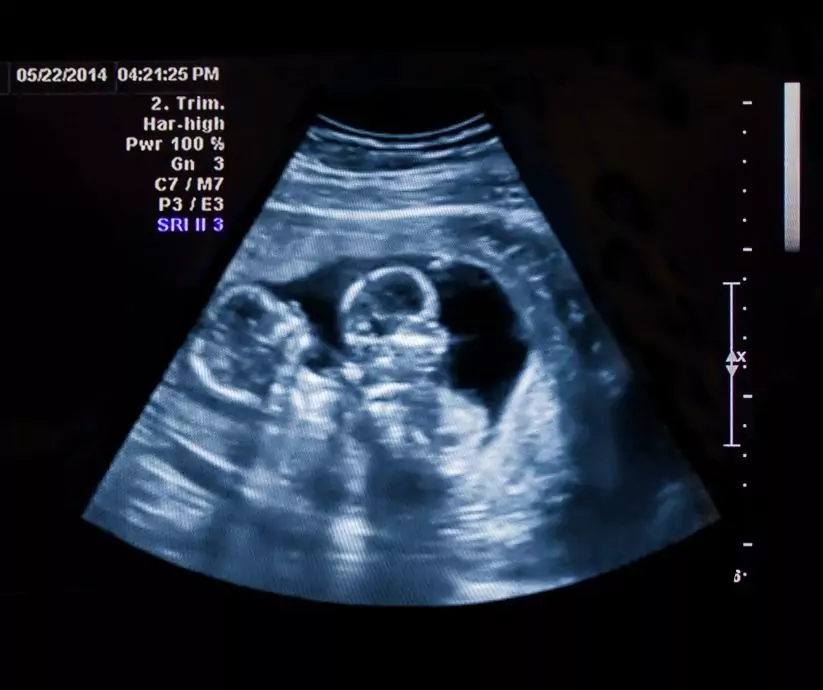

"Na wstępie warto zaznaczyć, że ciąża bliźniacza jest ciążą wysokiego ryzyka i powinna być ona prowadzona w specjalistycznym ośrodku. Ciąża ta wymaga szczególnego nadzoru położniczego – częstych badań USG, wykonywania zapisów KTG w zależności od rodzaju ciąży bliźniaczej – czasem nawet od 26. tygodnia ciąży. Poród siłami natury w przypadku ciąży bliźniaczej zależy w dużym stopniu od możliwości zapewnienia bezpieczeństwa matki i dziecka i ma na celu maksymalną redukcję urazów okołoporodowych." – wyjaśnia położna Martyna Zdunek.

Poród w ciąży bliźniaczej jest obecnie jednym z największych wyzwań współczesnego położnictwa. Retrospektywne analizy wskazują wyższe ryzyko powikłań przy porodach drogami natury w porównaniu do elektywnego zakończenia ciąży cięciem cesarskim. Nie potwierdzają jednakże tej zależności niedawno opublikowane wyniki wielośrodkowego badania randomizowanego Twin Birth Study. Badaniem objęto 2804 kobiet w ciążach bliźniaczych pomiędzy 32. a 39. tygodniem ciąży z położeniem główkowym pierwszego płodu. Nie stwierdzono istotnych statystycznie różnic w powikłaniach porodowych i noworodkowych pomiędzy badanymi grupami.

Obecnie do jedynych bezwzględnych wskazań do cięcia cesarskiego w ciąży bliźniaczej należą ciąża jednoowodniowa i bliźnięta nierozdzielone, jak również niegłówkowe położenie pierwszego płodu. W przypadku położenia miednicowego pierwszego płodu może dojść do kolizji płodów i chociaż to powikłanie występuje niezmiernie rzadko, to obarczone jest 30–40% ryzykiem zgonu płodów. Natomiast położenie miednicowe drugiego z płodów nie stanowi przeciwskazania do porodu drogami natury. W okresie przedporodowym trudno jest jednoznacznie ustalić położenie drugiego płodu, ponieważ w 20% przypadków po porodzie pierwszego z bliźniąt dochodzi do zmiany położenia drugiego.